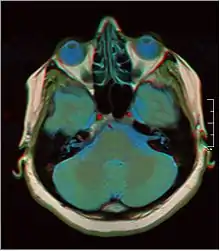

• T2-weighted (T2W) images: CSF is light, but fat (and thus white matter) is darker than with T1. T2-weighted images are useful for visualizing pathology.[25]

False color MRI by applying red to T1, green to PD and blue to T2.